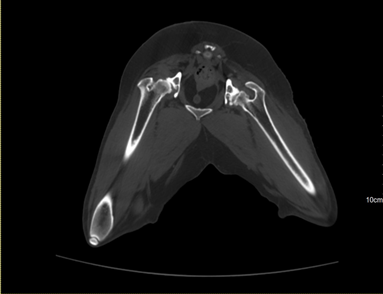

• Os